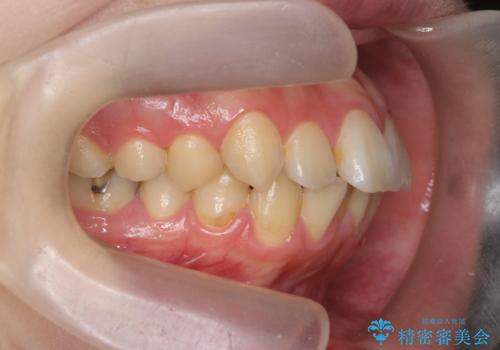

歯を抜かずに行う前歯の角度の改善

- 歯を抜かずに前歯の角度を改善したい、と矯正治療を希望され来院されました。

可及的に前歯部にIPR(歯間の削合)を行い、抜歯をせずマウスピース矯正システムインビザラインで歯の排列を行っていく治療計画としました。

治療の前後を比べると、がたつきや歯の角度が改善したことがしっかりと確認されました。